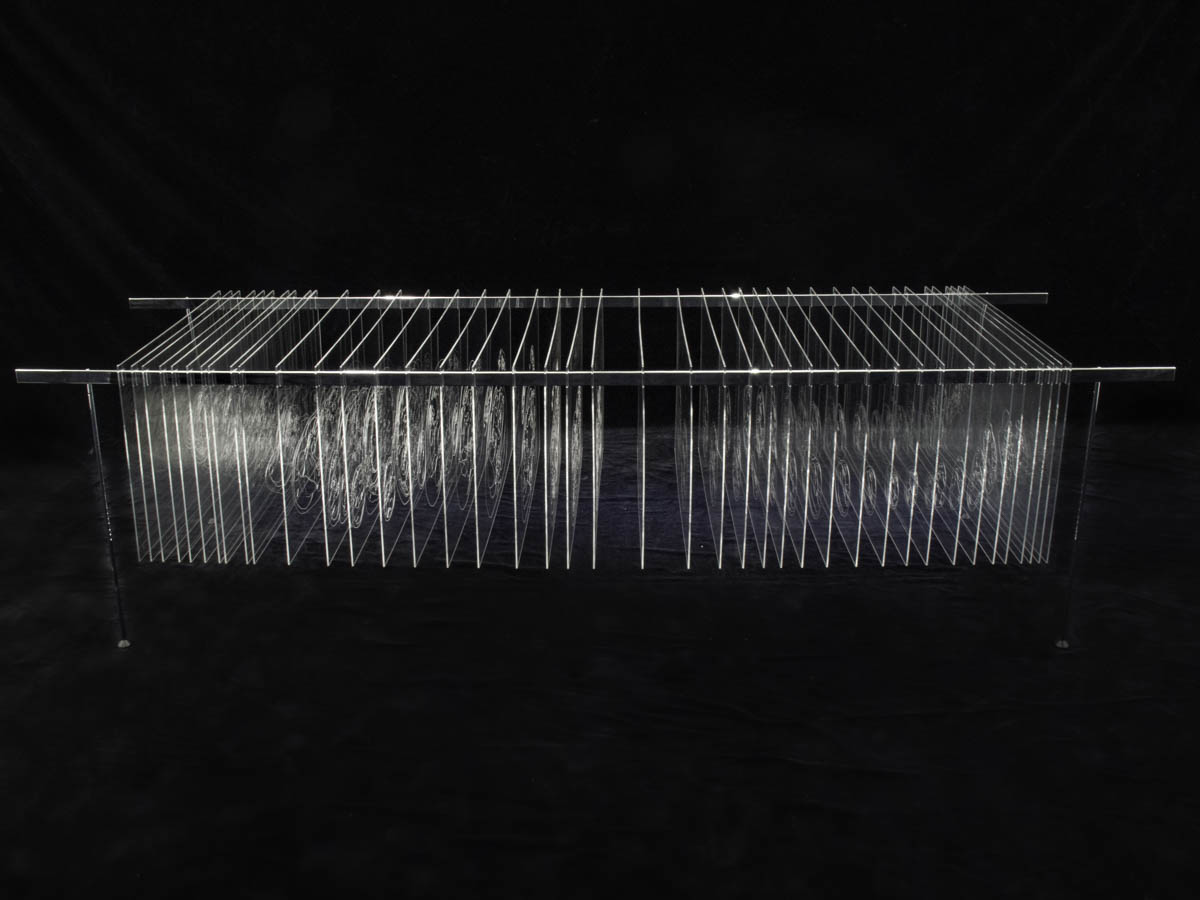

Découpe et gravure laser sur plexiglas, acier chromé 94 x 82 x 228 cm

41 coupes ont été sélectionnées et dessinées pour reformer le corps de Joseph Paul Jernigan, exécuté par injection au Texas en 1993. Ayant légué son corps à la science, il a été sectionné en 1878 tranches de 1 mm puis entièrement numérisé, ce qui a permis la création en 1994 du Visible Human Project, premier corps humain virtuel.